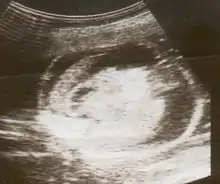

| An ultrasound showing a fetus with hydrops fetalis | |

Hydrops fetalis can be diagnosed and monitored by ultrasound scans.[1] An official diagnosis is made by identifying excess serous fluid in at least one space (ascites, pleural effusion, of pericardial effusion) accompanied by skin edema (greater than 5 mm thick). A diagnosis can also be made by identifying excess serous fluid in two potential spaces without accompanying edema. Prenatal ultrasound scanning enables early recognition of hydrops fetalis and has been enhanced with the introduction of MCA Doppler.[7]